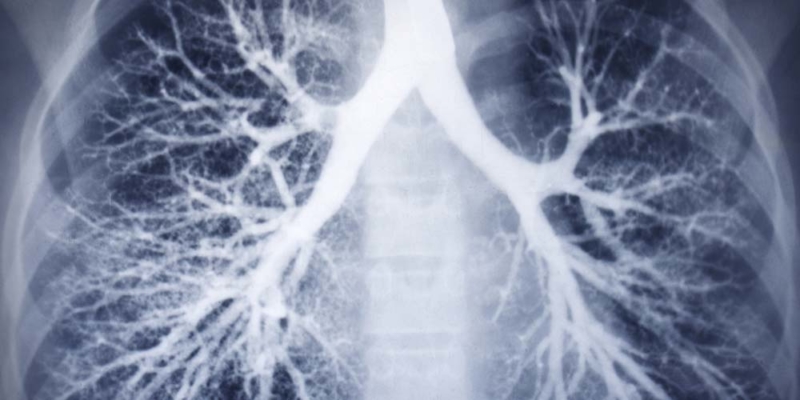

Are Your Lungs Shrinking?

When it comes to physical health, there are few things more important than “lung power.” Great martial artists like Bruce Lee knew physical strength and robust health depend on your lungs.

The strong men of my father’s era knew it too. Part of what gives you the capacity to live robustly is getting enough oxygen. But without your awareness, you are probably losing lung capacity. Your lungs tend to shrink with age.

By the time you reached 20, you stopped growing lung tissue and your lung capacity stabilized. This lasted for about 10 years. Then, around 30, your lungs started to decline. The alveoli that deliver oxygen to your blood began to die off. Slowly, most folks limit their daily activities so their lungs can keep up.

Unless you prevent it, you lose 20 percent of your vital lung capacity by about age 35. By 50, you’ve lost 40 percent of your breathing capacity and the decline continues for life.

What’s more, bigger lungs supply your working body with more oxygen. They also restore cell health by removing cell-eroding carbon dioxide. When there’s plenty of oxygen circulating around the body, your muscles can afford to use it to build reserve sources of energy for times of stress or exertion. But as your lung capacity decreases, your normal everyday activity takes up more of it, leaving you with very little reserve.